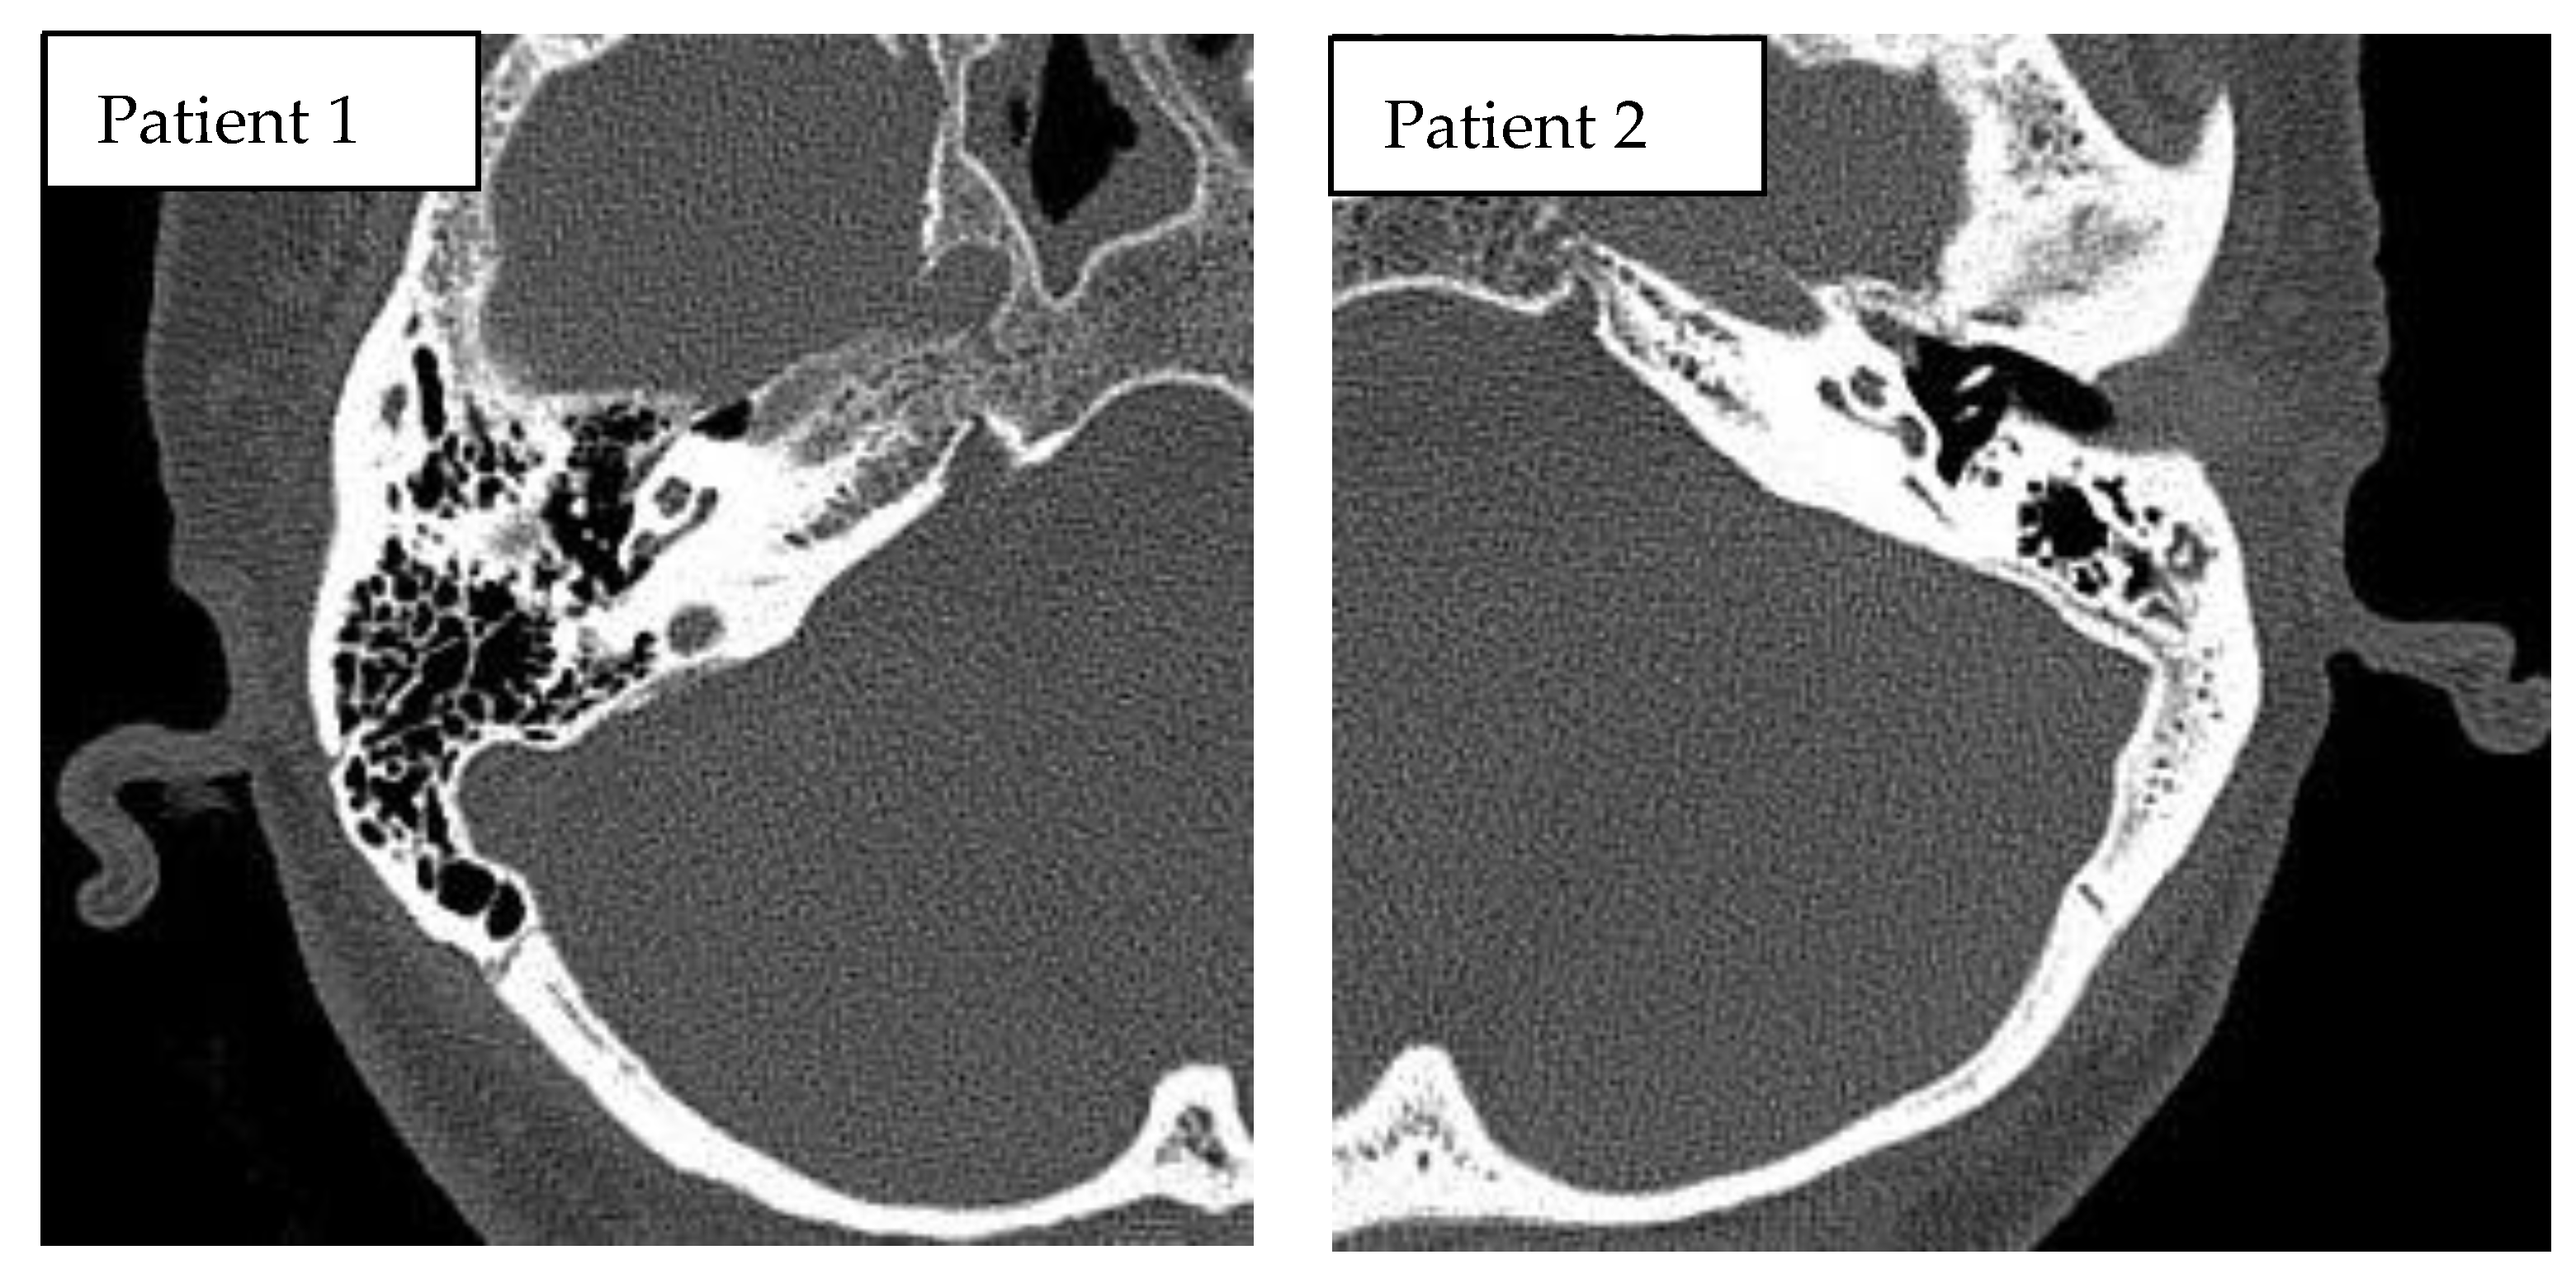

This prospective, pilot study included two adult patients (females, aged 57 and 61 years) who underwent cochlear implantation in a tertiary referral center. Robot-assisted cochlear implantations were performed on 12–13 July 2022. The surgeries were preceded by surgical training on an artificial temporal bone (Figure 1). The patients had passed the typical procedure for qualifying for a cochlear implant at our center before surgery. Both patients had residual hearing in the implanted ear (Figure 2). The preoperative CT of the temporal bone (Siemens, Somatom Definition Edge, Munich, Germany) showed normal anatomy of the ear qualified for cochlear implantation in the both cases (case 1–right ear, case 2–left ear) (Figure 3). The patients provided informed, written consent for their participation in the study and the publication of its findings. The study was approved by the local Bioethics Committee (decision number 1033/19).

Figure 3.

Preoperative CT of temporal bones of the patients, both cases with normal anatomy of the temporal bone.